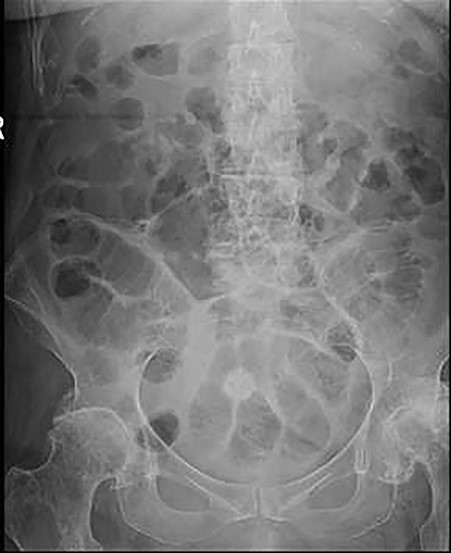

As the gallstone was seen within the ascending colon, the patient was managed conservatively for 2 days after which she was able to tolerate fluids then light diet. Follow-up abdominal X-ray revealed that the gallstone had reached the rectum with no radiological signs of bowel obstruction (Fig. 3). On the fourth day of admission, she opened her bowels and abdominal distension completely resolved.

Follow-up abdominal X-ray revealed the gallstone in the rectum and that bowel obstruction has now resolved.